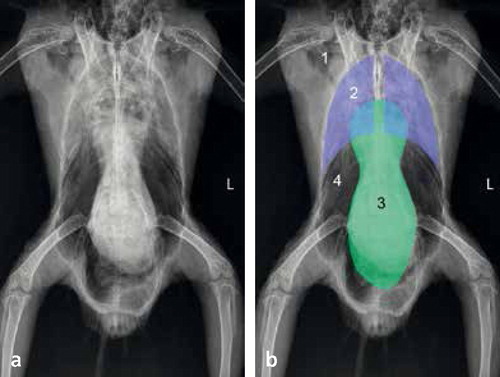

پس از یک معاینه کامل فیزیکی ، دامپزشک پرندگان ممکن است یک رادیوگرافی با استفاده از باریم به نام رادیوگرافی کنتراست انجام دهد. این آزمایش ممکن است یک پیش معده بزرگ و ملتهب را نشان دهد. آزمایشات دیگری وجود دارد که می توان به آنها اعتماد کرد ، مانند آزمایش خون برای برنا ویروس در پرندگان ، که ممکن است احتمالاً تشخیص شرایط پرنده شما شود.